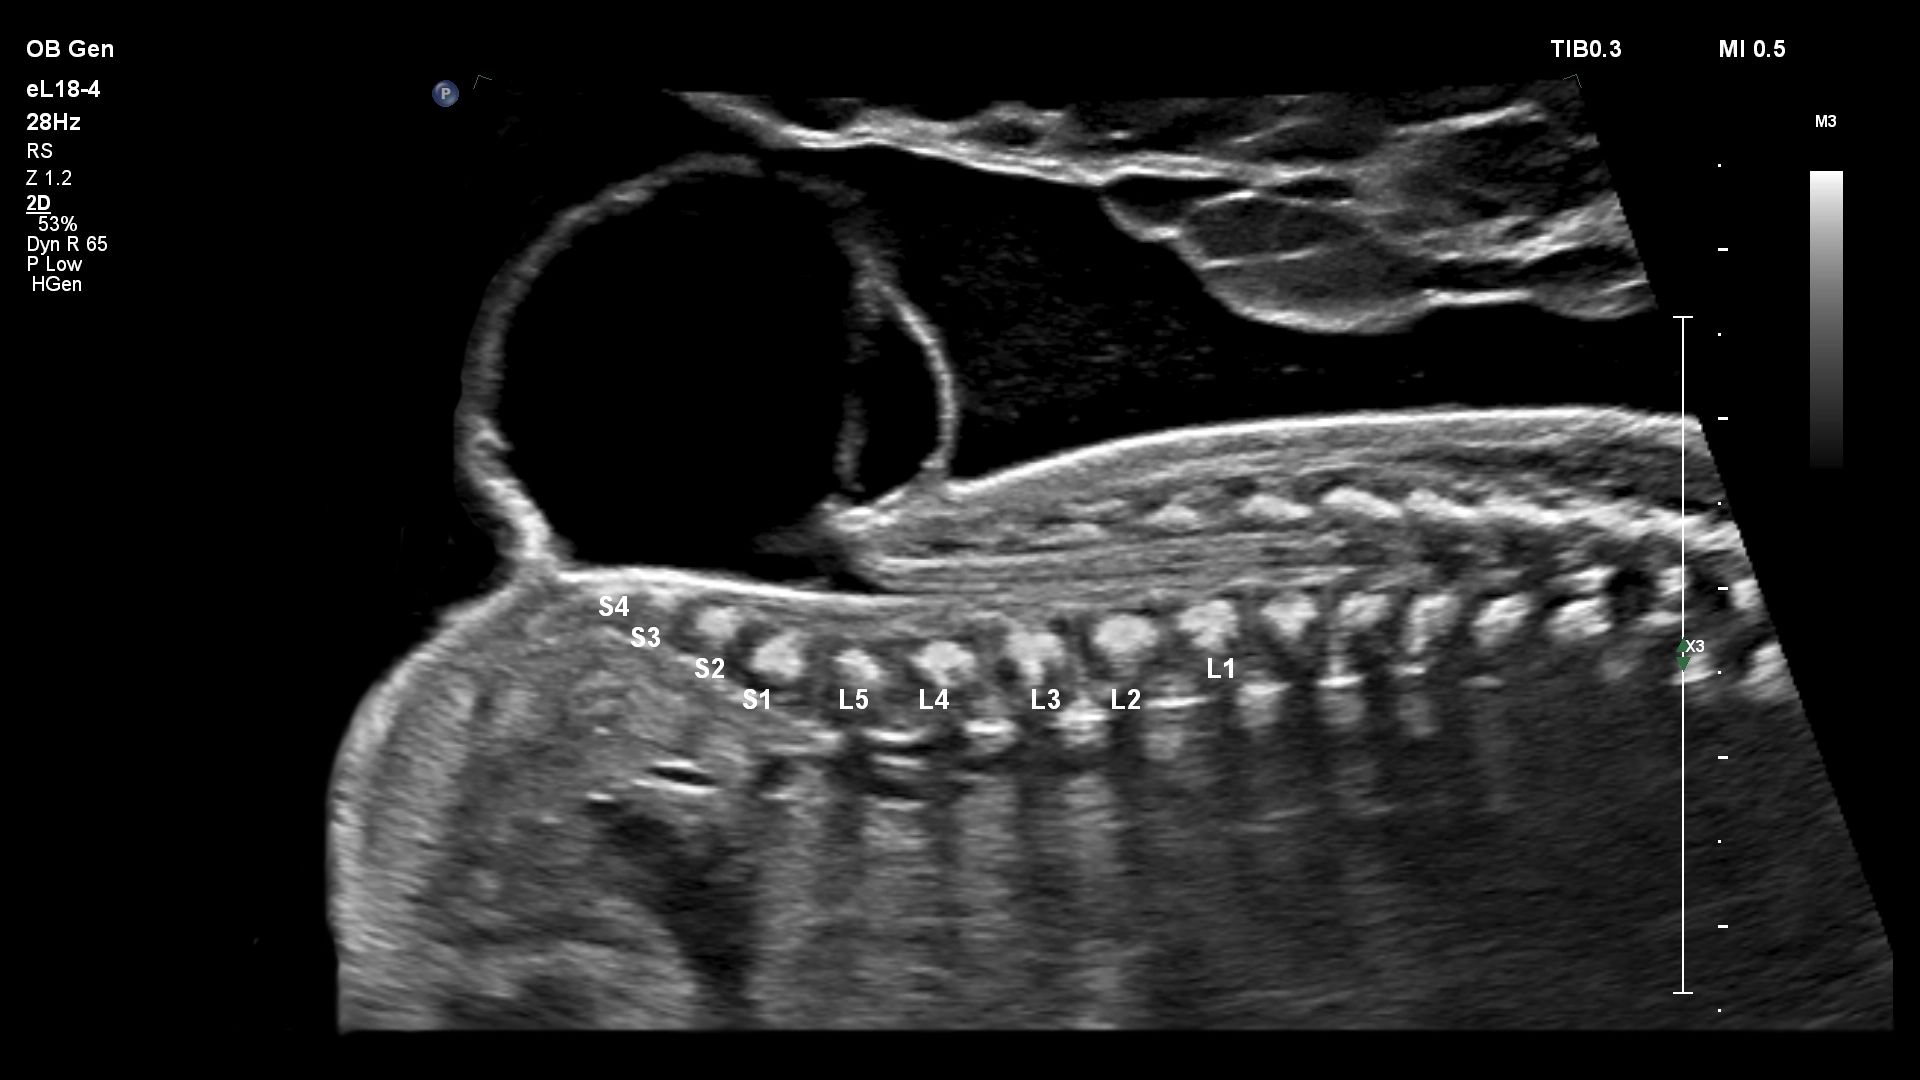

- Акушерство

Функции для гинекологии и акушерства

- Free Hand 3D - возможность реконструкции 3D изображения при помощи линейного или конвексного датчика

- 4D Imaging - автоматическая визуализация 3D/4D изображения

- aBiometry Assist - автоматические биометрические измерения